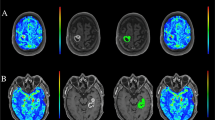

A total of 97 subjects were included in the study of whom 73 had high-grade gliomas, 12 had low-grade gliomas and 12 had solitary brain metastases. Cohort demographic, clinical and radiological features are listed in Table 1. As indicated in Fig. 2, a statistical difference was found for DSC-PWI nCBF (p < 0.001), DSC-PWI nCBV levels, DSC-PWI nK2, CTP nCBF, CTP nCBV (p < 0.01) and CTP nPS (p < 0.001) among high-grade gliomas, low-grade gliomas and metastases. In particular, high-grade gliomas had significantly higher values for DSC-PWI nCBF, DSC-PWI nCBV (p < 0.001) and DSC-PWI nK2 (p < 0.01) than low-grade gliomas (Fig. 2, panel A), whereas DSC-PWI nCBV levels were statistically more elevated in metastases than in low-grade gliomas (p < 0.05). On the other hand, while high-grade gliomas had significantly greater CTP nCBF (p < 0.01), CTP nCBV (p < 0.001) and CTP nPS (p < 0.01) levels than in low-grade glioma, metastases had more increased CTP nCBF (p < 0.05), CTP nCBV (p < 0.01) and CTP nPS (p < 0.0001) values than low-grade gliomas and more prominent CTP nPS levels than high-grade gliomas (Fig. 2, panel B). A strong positive correlation was detected between DSC-PWI nCBF and CTP nCBF, as well as between DSC-PWI nCBV and CTP nCBV values (p < 0.00001), whereas less pronounced (p < 0.01) was the association between DSC-PWI nK2 and CTP nPS levels (Fig. 3). As shown by bias and 95% limits of agreement values of Bland–Altman plots (Fig. 4), the agreement was strong between DSC-PWI nCBF and CTP nCBF, good between DSC-PWI nCBV and CTP nCBV and poorer between DSC-PWI nK2 and CTP nPS levels.

Panel A Scatter plots showing magnetic resonance dynamic susceptibility contrast perfusion-weighted imaging (PWI) normalized cerebral blood flow (nCBF), normalized cerebral blood volume (nCBV) and normalized capillary transfer constant (nK2) values in patients with high-grade gliomas (High grade), low-grade gliomas (Low grade) and metastases. The horizontal line marks the median. Panel B Box plots illustrating computed tomography perfusion (CTP) nCBF, nCBV and normalized permeability surface area product (nPS) values in patients with high-grade gliomas (High grade), low-grade gliomas (Low grade) and metastases. The boundaries of the boxes represent the 25th–75th quartile. The line within the box indicates the median. The vertical lines above and below the box correspond to the highest and lowest values, excluding outliers